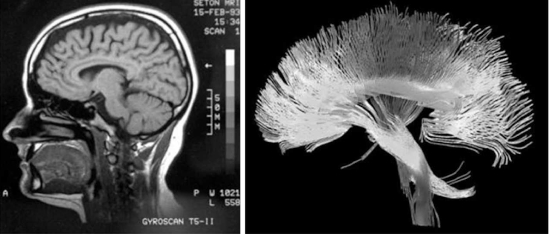

Como la invención del telescopio, la aparición, a mediados de la década de 1990 y en la primera década del siglo XXI, de las máquinas de imagen por resonancia magnética (MRI, por sus siglas en inglés: Magnetic Resonance Imaging) y una variedad de sofisticados escáneres cerebrales ha transformado la neurociencia. Hemos aprendido más sobre el cerebro en los últimos quince años que en toda la historia humana, y la mente, antes considerada fuera de nuestro alcance, empieza por fin a ocupar su lugar bajo los focos.

Esta descripción del cerebro representa aproximadamente lo que sabíamos de él en la década de 1980. Sin embargo, durante la década de 1990, con la introducción de nuevas tecnologías procedentes del campo de la física, se empezó a revelar en detalle la mecánica de los pensamientos, lo que desencadenó la explosión de descubrimientos científicos que estamos viviendo actualmente. Uno de los pilares de esta revolución ha sido la obtención de imágenes por resonancia magnética (MRI, por sus siglas en inglés: Magnetic Resonance Imaging).

Las ondas de radio, un tipo de radiación electromagnética, pueden atravesar los tejidos sin dañarlos. Los aparatos de imagen por resonancia magnética se sirven de este principio, que permite que las ondas electromagnéticas penetren sin problemas en el interior del cráneo. Al hacerlo, esta tecnología nos ha permitido obtener fantásticas imágenes que en otro tiempo habríamos creído imposibles de conseguir: el funcionamiento interno del cerebro mientras experimenta sensaciones y emociones. A partir del parpadeo de las luces en un aparato de imagen por resonancia magnética se puede trazar el recorrido de los pensamientos a través del cerebro. Es como ser capaces de observar el interior de un reloj que marca las horas.

Puesto que los distintos compuestos químicos responden a diferentes frecuencias de radio, variando la frecuencia del pulso de radio se pueden identificar los distintos elementos del cuerpo. Como ya hemos visto, las máquinas de imagen por resonancia magnética funcional se centran en los átomos de oxígeno de la sangre para medir el flujo sanguíneo, pero los aparatos de imagen por resonancia magnética se pueden sintonizar para identificar otros átomos. En la última década, ha aparecido una nueva forma de imagen por resonancia magnética denominada «de difusión» (DTI, por sus siglas en inglés: Diffusion Tensor Imaging), que detecta el flujo de agua en el cerebro. Como el agua recorre las vías nerviosas del cerebro, esta nueva técnica permite obtener imágenes fantásticas, que recuerdan a las redes de parras que crecen en un jardín. Los científicos pueden determinar al instante cómo están conectadas entre sí distintas partes del cerebro (véase figura 5). No obstante, la tecnología de imagen por resonancia magnética presenta algunos inconvenientes. Aunque su resolución espacial es insuperable y permite localizar en tres dimensiones vóxeles del tamaño de la cabeza de un alfiler, su resolución temporal no es tan buena. Se tarda casi un segundo en seguir el recorrido de la sangre por el cerebro, lo que puede que no parezca mucho, pero recordemos que las señales eléctricas recorren el cerebro de manera casi instantánea, por lo que es posible que los escáneres de imagen por resonancia magnética no permitan distinguir los intrincados detalles de los patrones de pensamiento.

Figura 5. La imagen izquierda (AP Photo David Duprey), obtenida con un aparato de resonancia magnética funcional, refleja regiones de alta actividad mental. La imagen derecha (Tom Barrick, Chris Clark/Science Source), cuya forma es similar a una flor, ha sido generada por un aparato de resonancia magnética por difusión, capaz de seguir las vías nerviosas y las conexiones del cerebro.